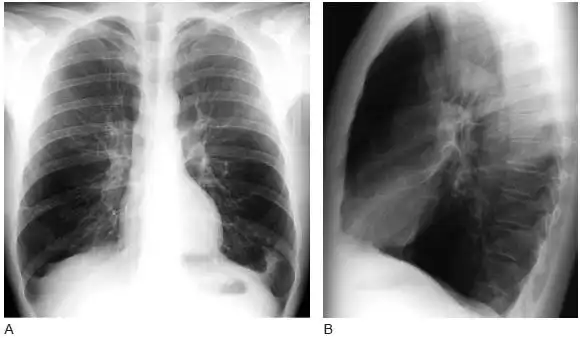

34 岁男性,继发于α1- 抗 胰蛋白酶缺乏症的全小叶型肺气肿患者